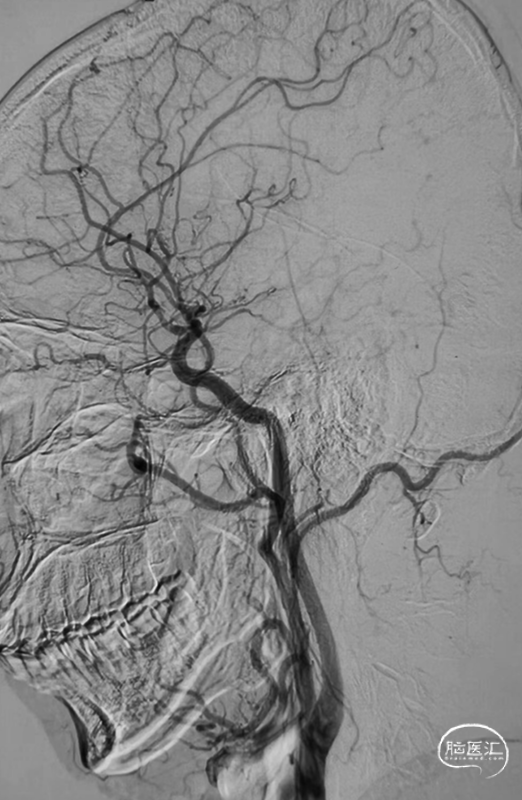

➢脑血管DSA

➢RCCA